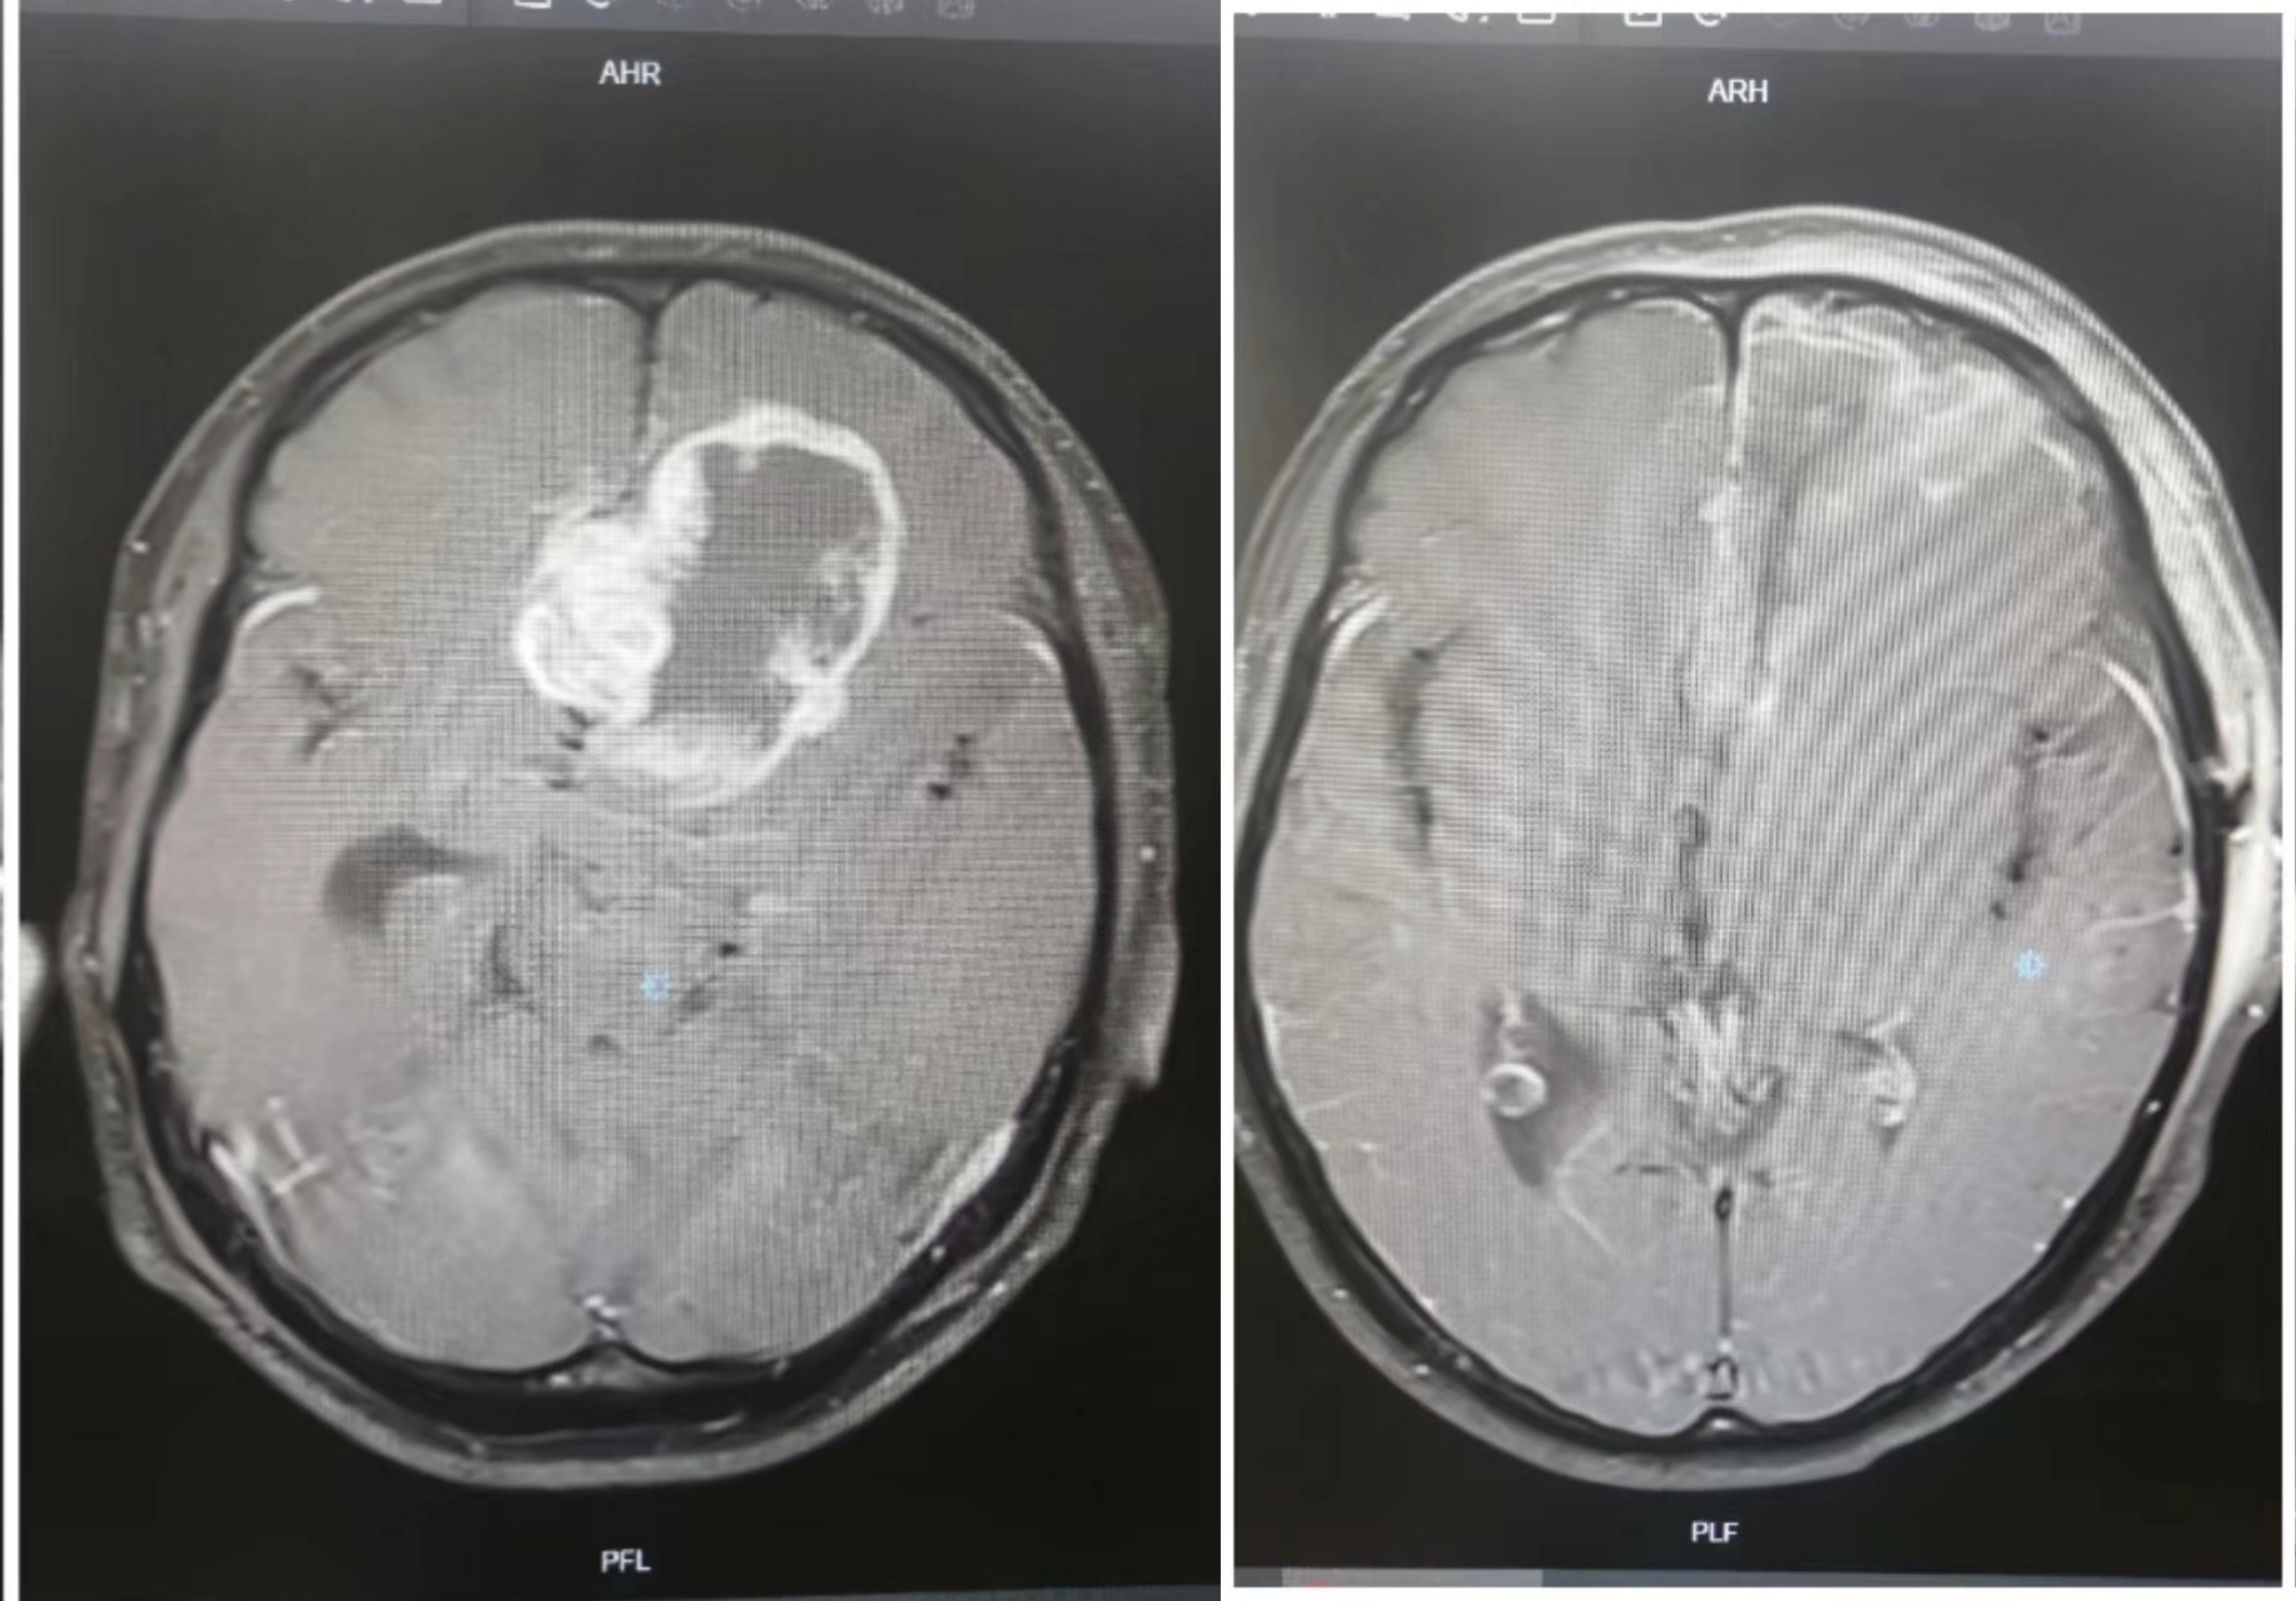

左侧额颞顶叶占位

右侧丘脑、胼胝体胶质瘤

左侧额顶叶占位

右侧额顶叶占位